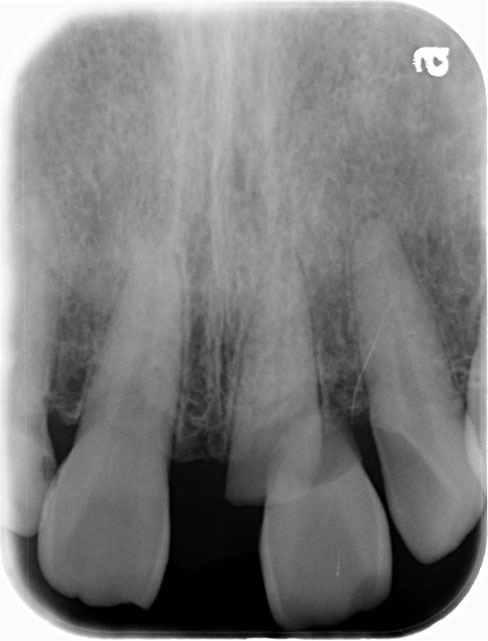

レントゲン写真

| 治療方法 | レントゲンで精査すると歯根が破折しており保存不可能なので抜歯。 もともと正中離開し審美的にも不良であった。正中離開した状態でそのまま治すのかこの際、審美的にも改善したいのか2つのオプションを提示すると矯正治療をした上で完璧に治したいとの要望があったので矯正治療を行いインプラント治療する計画を立てた。両隣在歯3本はジルコニアセラミック審美治療を行った。 |